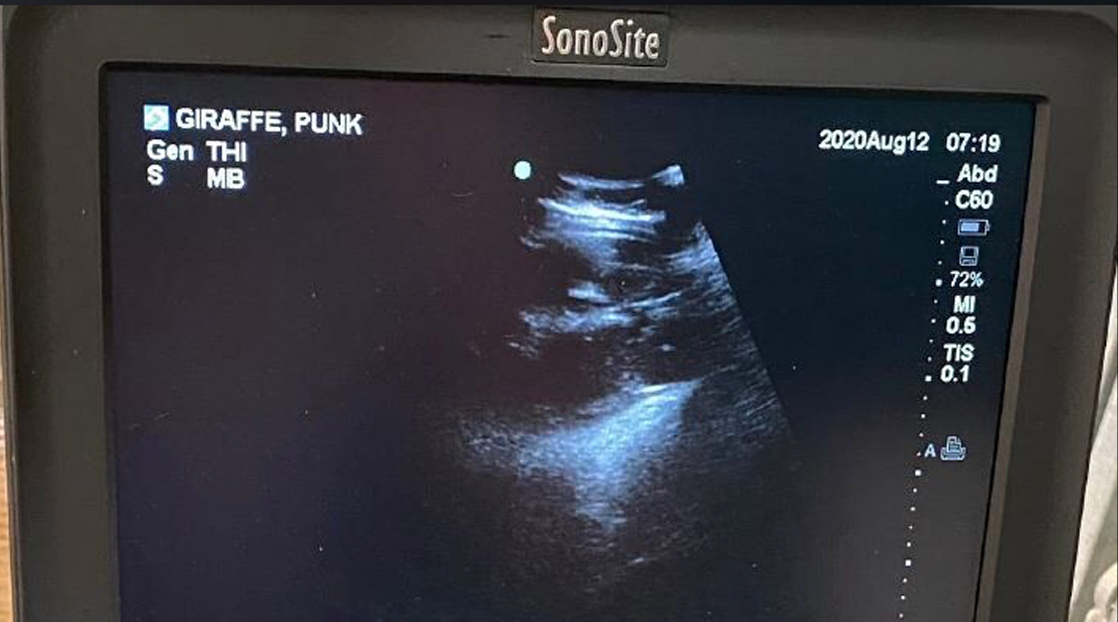

According to the zoo, Jaime and Punk could give birth later this month. The third giraffe, Sunny, has not allowed zoo staff to confirm her pregnancy with a blood test.